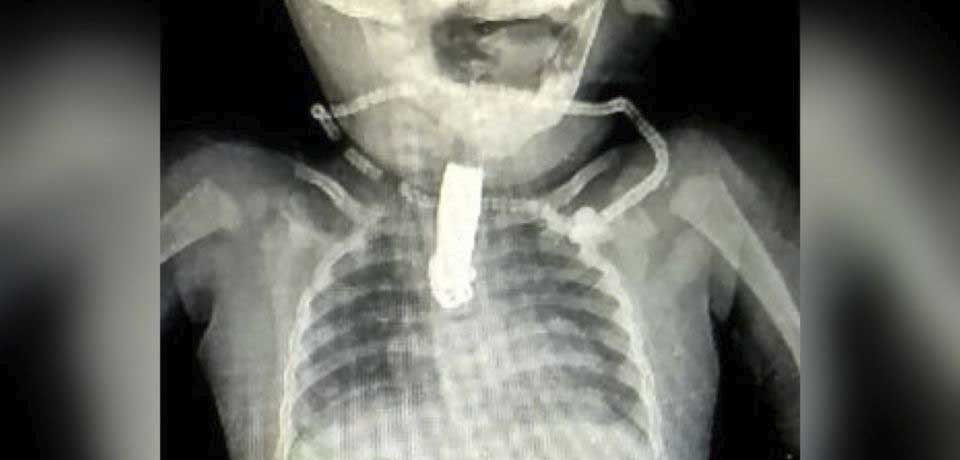

De inmediato, los médicos le realizaron una radiografía, la cual mostró que, efectivamente, el cortaúñas se encontraba alojado en su garganta.

La bebé tuvo que ser sometida a una operación para que le pudieran retirar el objetivo, cirugía que resultó ser exitosa.